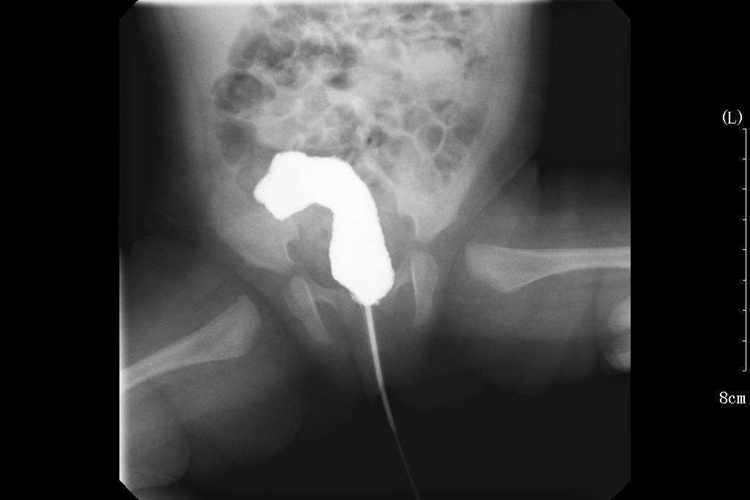

婴儿肛门狭窄主要表现为大便不畅、便条变细、便秘或肛门部不适、疼痛症状,有时伴有腹胀、呕吐等;肛门指检时可发现直肠、肛门有不同程度的狭窄,狭窄严重者手指不能通过;内镜检查时可见狭窄部黏膜呈灰白色,并肥厚变硬。

导致婴儿肛门狭窄的病因较多,如先天性畸形,在胚胎发育过程中,直肠和肛管之间的肛膜未破裂或不全破裂,可出现肛门狭窄。直肠肛门的各种慢性炎症和溃疡,可使直肠壁及肛门形成瘢痕,进而挛缩造成直肠肛门狭窄,如肛门直肠周围脓肿、肛门直肠瘘、直肠溃疡,各种直肠炎、直肠结核等。外伤或者手术等也可导致疤痕组织增生,形成肛门狭窄。

婴儿肛门狭窄需在医生指导下治疗。可通过使用通便类药物治疗,排除积存的粪便及保护已形成的溃疡面,轻度肛门及直肠下端环状狭窄,可通过手指进行扩肛处理,若婴儿肛门狭窄较为严重,或非手术治疗无效者,可采用经后矢状入路肛门直肠成形术,或经骶腹会阴肛门成形术等治疗。